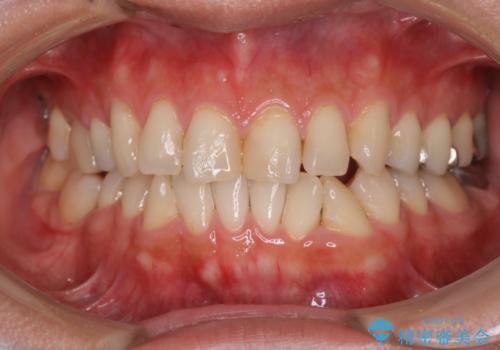

[マウスピース矯正] がたがたの歯並びをきれいにしたい

![[マウスピース矯正] がたがたの歯並びをきれいにしたいの症例 治療前](https://seimitsushinbi.jp/wp/wp-content/uploads/2025/06/0d238550c8a0fddc4de7b2c337c6c786-500x350.jpg?v=1750323380)

![[マウスピース矯正] がたがたの歯並びをきれいにしたいの症例 治療後](https://seimitsushinbi.jp/wp/wp-content/uploads/2025/06/IMG_0002-2-500x350.jpg?v=1750323305)